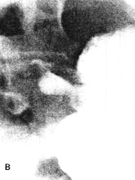

Case 32.1. E.B., 5 weeks old female infant, was admitted with a history of vomiting after feeds and recurrent bilateral pneumonia. Radiographic examination showed a severe, constant narrowing of the pyloric sphincteric cylinder, with a "string sign" typical of IHPS (Fig. 32.1A). The gastro-oesophageal junction was patulous with free and persistent gastro-oesophageal reflux, diagnosed radiographically as a sliding hiatus hernia (Fig. 32.1B). Some aspiration of refluxed barium occurred. At operation the next day a pyloric "olive" measuring approximately 2.3 cm x 0.8 cm, typical of IHPS, was found. Ramstedt pyloromyotomy was done; post-operatively vomiting stopped and the patient made an uneventful recovery.

| Fig. 32.1 A,B. Case E.B. A Constant narrowing of pyloric sphincteric cylinder with string sign (arrows), typical of idiopathic hypertrophic pyloric stenosis. B Patulous gastro-oesophageal junction with free reflux (arrow) |